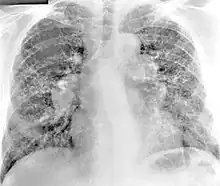

X-ray image of a 54-year-old man working in the aerospace manufacturing industry with berylliosis

Diagnosis of berylliosis is based on history of beryllium exposures, documented beryllium sensitivity, and granulomatous inflammation on lung biopsy. Given the invasive nature of a lung biopsy, diagnosis can also be based on clinical history consistent with berylliosis, abnormal chest x-ray or CT scan findings, and abnormalities in pulmonary function tests.[16]

Chest radiography findings of berylliosis are non-specific. Early in the disease radiography findings are usually normal. In later stages interstitial fibrosis, pleural irregularities, hilar lymphadenopathy and ground-glass opacities have been reported.[20][21] Findings on CT are also not specific to berylliosis. Findings that are common in CT scans of people with berylliosis include parenchymal nodules in early stages. One study found that ground-glass opacities were more commonly seen on CT scan in berylliosis than in sarcoidosis. In later stages hilar lymphadenopathy, interstitial pulmonary fibrosis and pleural thickening.[21]